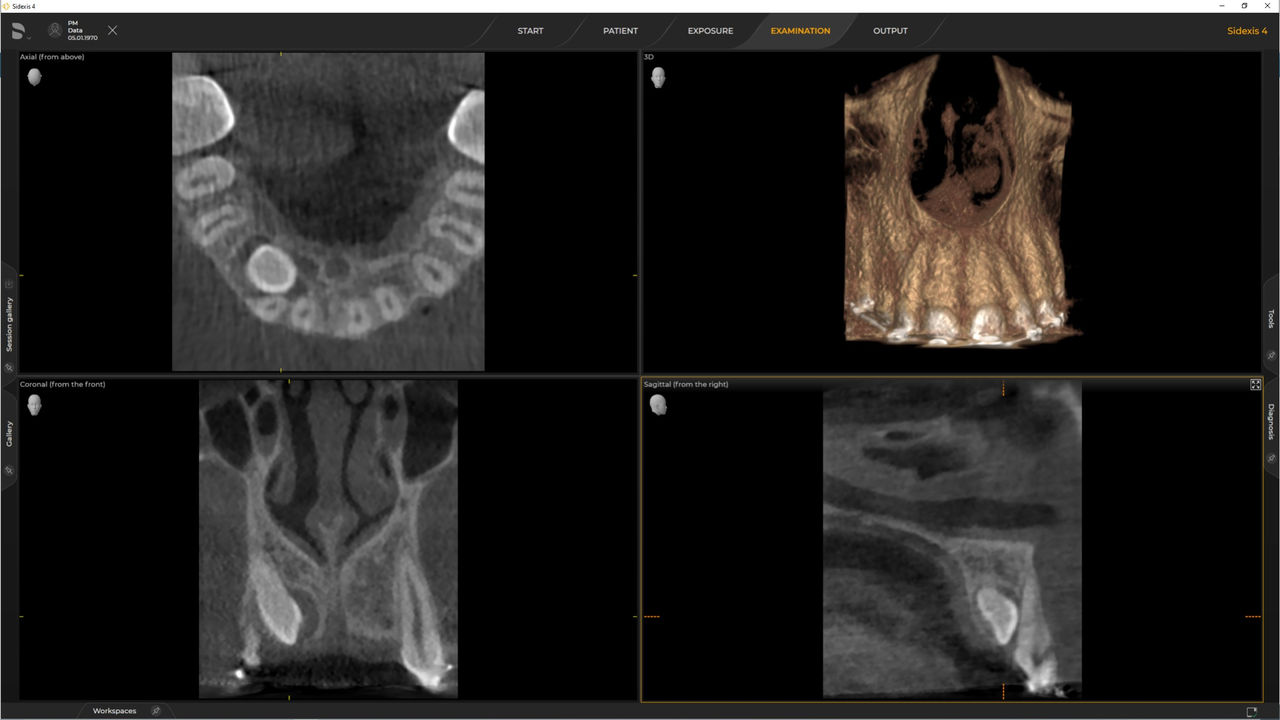

Las unidades de radiología de Dentsply Sirona funcionan exclusivamente con Sidexis 4. Sin embargo, la migración de datos de Sidexis XG a Sidexis 4 es muy fácil. Sidexis 4 permite una experiencia digital completa con las últimas herramientas

Una amplia gama de tamaños de volumen para satisfacer sus diversas necesidades clínicas y de diagnóstico, desde Ø 5 x 5,5 cm hasta Ø 11 x 10 cm